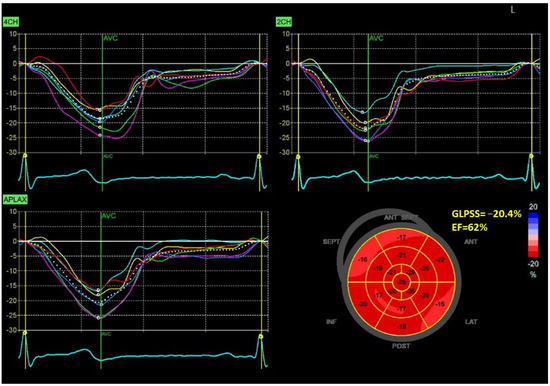

Figure 1 and Figure 2 show two contrasting examples (a healthy person and a patient after myocardial infarction and left bundle branch block) of STE curves with GLPSS, LVEF and LV pressure–strain loops and results of GWE for all LV segments.

Figure 2.

An example of echocardiography of a 61-year-old man with the left bundle branch block and a history of myocardial infarction. A set of individual longitudinal strain curves for all segments shown in different colors, with the average curve shown as a white dotted line, a bull’s eye of segmental longitudinal peak systolic strains and a summary of global longitudinal peak systolic strain (GLPSS) are shown in the top panel. The LV pressure–strain loop with the bull’s eye representation of myocardial work efficiency for each of the segments and a summary of all myocardial work indices are shown in the lower panel. Abbreviations: GLS—global longitudinal peak systolic strain, EF—ejection fraction, GWI—global myocardial work index, GCW—global constructive work, GWW—global wasted work, GWE—global work efficiency, BP—blood pressure.